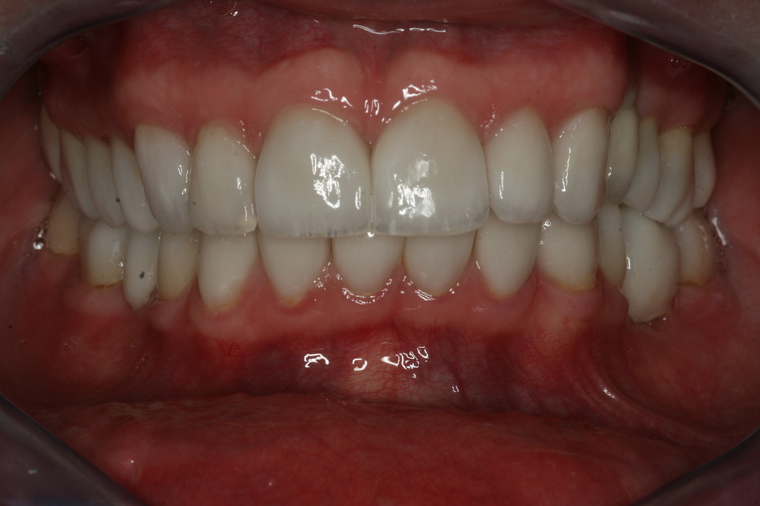

Generalsanierung

Viele Kunden die zu uns nach Salzburg kommen benötigen eine Generalsanierung der Zähne. Gründe dafür sind Zahnarztangst, Zeitmangel und schlechte Erfahrungen in der Kindheit. Unser Konzept ist genau auf diese umfangreichen Fälle abgestimmt:

Bei einer Generalsanierung müssen alle zahnmedizinischen Bereich in Betracht gezogen werden, dies beginnt bei der Aufklärung und Prophylaxe, gefolgt von Zahnfleischbehandlungen und Kariestherapie, eventuellen Zahnentfernungen, Knochenaufbauten und wird durch ästhetischen Zahnersatz abgeschlossen. Unser Recall-System hält die erreichte Zahnsanierung über lange Jahre stabil.